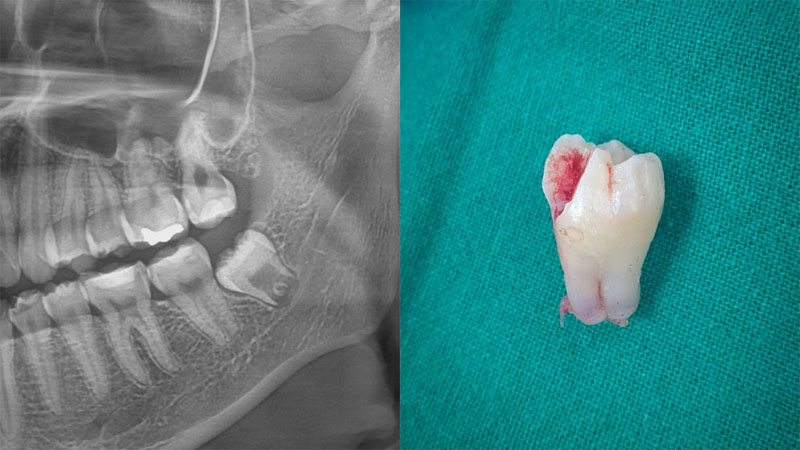

۱. جراحی دندان عقل

جراحی دندان عقل یکی از رایجترین انواع جراحیهای دندان است که معمولاً برای خارج کردن دندان عقل نهفته یا دندانی که به طور کامل رشد نکرده است انجام میشود. این جراحی زمانی ضروری میشود که دندان عقل به سایر دندانها فشار وارد کند، موجب عفونت یا التهاب لثه شود یا به دلیل کمبود فضای کافی در فک، به طور نادرست رشد کند. معمولاً این جراحی با بیحسی موضعی انجام میشود و دوره بهبودی آن چند روز تا یک هفته طول میکشد.

۴. برداشتن یا ترمیم دندان

اگر دندان باید کشیده شود، ممکن است به قطعات کوچکتر تقسیم شود تا با کمترین آسیب به بافتهای اطراف برداشته شود. در صورتی که هدف جراحی ترمیم دندان باشد، مانند ریشهدرمانی یا درمان کیست، اقدامات لازم انجام میشود.